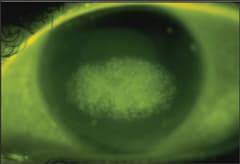

Clinicians have reported cases of patients who, after months of successful overnight corneal reshaping, present with acute episodes of ocular pain and central corneal abrasions (Figure 1). Lens inspection in these cases reveals areas of deposits on the posterior lens surface for the affected eyes.

Figure 1. Corneal abrasion caused by posterior surface lens deposits.